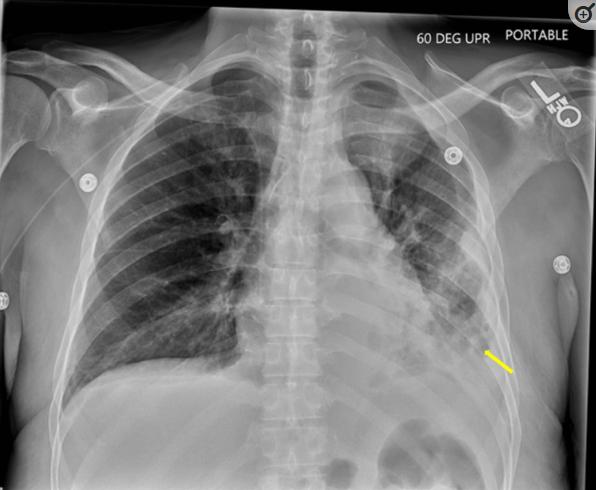

患者男性,60岁,既往有胰腺炎、酒精使用障碍、高血压、痛风和甲状腺功能减退症病史,因上腹部疼痛并向背部放射而被送往急诊科。患者还报告了就诊上周最低限度的口服摄入、带有绿色痰的咳嗽以及大量饮酒史(一次/天)。到达急诊室时,心动过速至每分钟130次,低血压至98/60 mmHg,低氧血症伴呼吸功增加,血氧饱和度为90%。胸部计算机断层扫描(CT)显示左肺下叶(LLL)几乎完全实变,左后心尖部胸腔积液(图1)。入院时,血清肌酐水平升高至4.77mg/dL,乳酸水平升高至4.4mmol/L。开始接受经验性的头孢吡肟、阿奇霉素和甲硝唑治疗,并住进重症监护室接受进一步治疗。

图1、胸部计算机断层扫描显示左肺下叶几乎完全实变,左后心尖部胸腔积液